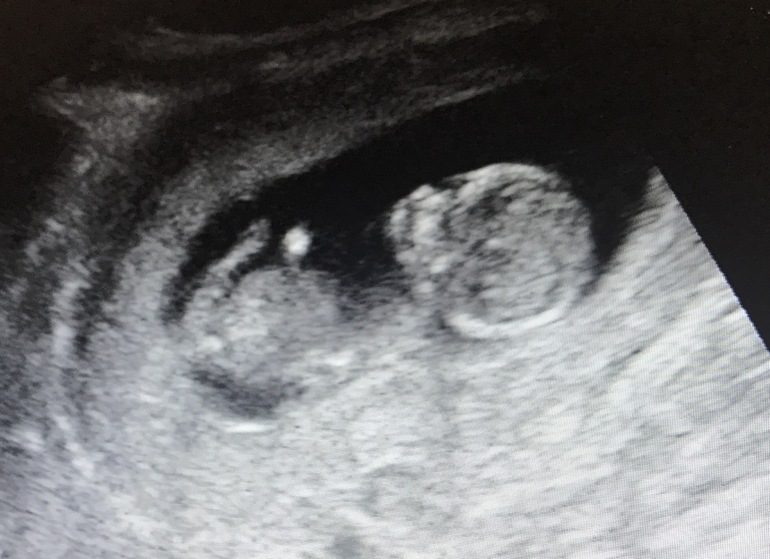

Была на УЗИ сегодня. По М 12,2сегодня. По УЗИ сказали полных 13 (прошлое УЗИ наоборот на неделю меньше показало) Малышок (КТР) 53мм всего. Поацента и матка отлично. Все хорошо. Носик и головка - все хорошо. Крошка там ручками личико трогает, ножками толкается, это так мило... первый раз видела. Пол не видно особо, но немного похож на М. Посмотрим ещё через 3 недельки)

Вот пару фото: